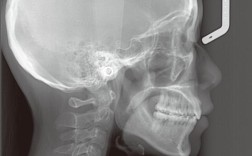

- 影像学检查:拍摄全景片观察牙根位置、牙槽骨情况;头颅侧位片进行头影测量(如SNA、SNB、ANB角分析颌骨关系,上下中切牙轴倾度评估牙齿位置);CBCT可三维显示颌骨形态,尤其适用于骨性偏移评估。